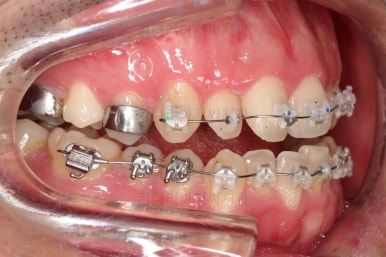

수술 전 교정과정이 거의 마무리 되어 갑니다.

오히려 앞니가 거꾸로 물리는 정도는 더 심해지고요.

수술 직전이 얼굴모습도 가장 주걱턱이 심한 양상으로 됩니다.

농담 삼아 못생겨지면 못생겨질수록 수술이 더 잘될겁니다 라고 말씀 드립니다.

수술 전 교정 7개월 -> 수술 및 회복 1개월 -> 수술 후 교정 7개월